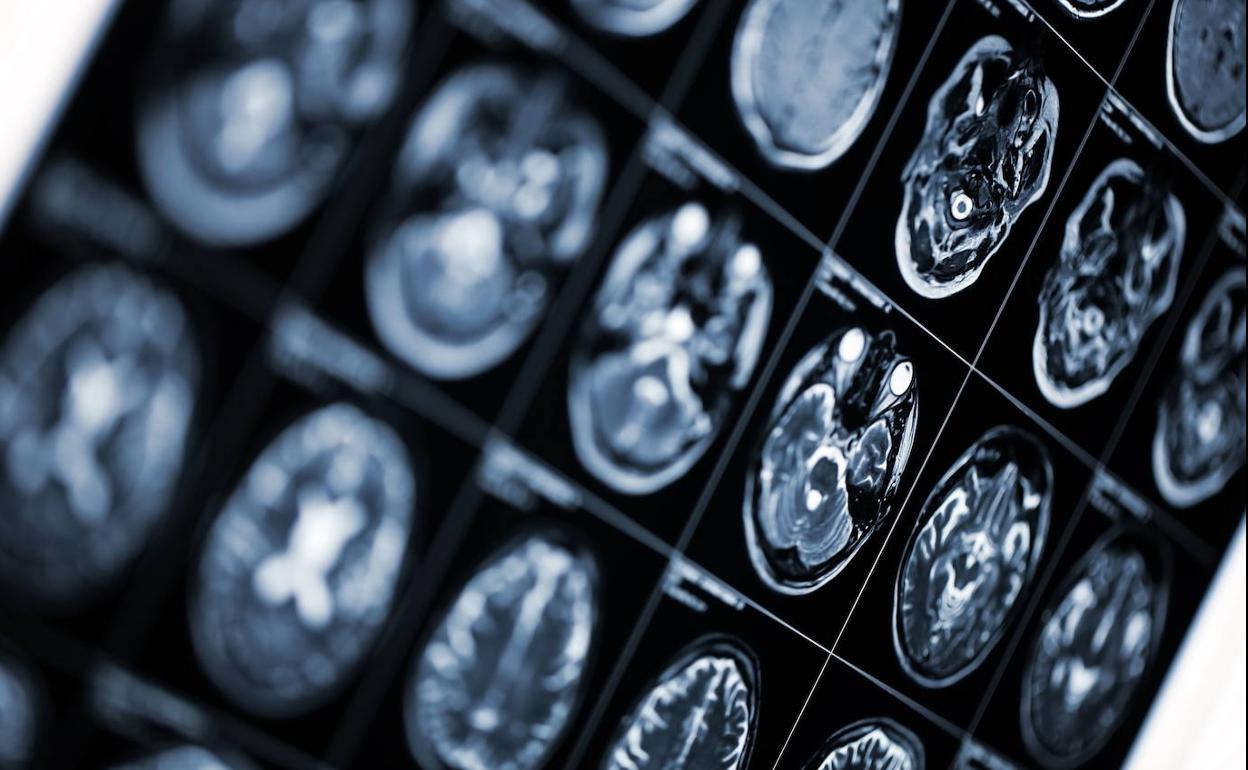

Gobierno y autonomías aprueban el primer plan nacional contra el alzhéimer

La estrategia 2019-2023, que no cuenta con una financiación específica, busca mejorar el diagnóstico precoz y la atención a los enfermos y los familiares que les cuidan

El Gobierno y las autonomías aprobaron este jueves el Plan Nacional de Alzhéimer y Otras Demencias a través de sus representantes en el Consejo Territorial de Servicios Sociales. Este plan, el primero de su clase en España, recoge los objetivos y las medias con las que se pretende aumentar el diagnóstico temprano de esta enfermedad, que padecen unos 800.000 españoles, y mejorar la atención integral a los afectados por la dolencia y a los cientos de miles de familiares que los cuidan.

El plan diseña la implantación de políticas preventivas contra la enfermedad y busca mejorar la capacidad de diagnóstico precoz que, en la actualidad, según los expertos, no alcanza a entre un 30% y un 40% de quienes ya padecen las primeras fases de la dolencia. Se trata de una enfermedad aún sin cura, pero sí hay tratamientos que lograr ralentizar o detener durante años la progresión del alzhéimer, por lo que detectarlo pronto puede mejorar de forma notable la salud y la calidad de vida del enfermo. Una de las medidas será formar a los profesionales sanitarios para que detecten pronto síntomas y signos que pueden alertar de la enfermedad. La estrategia nacional también fomentará la investigación sobre las causas, la prevención y el tratamiento de las demencias.